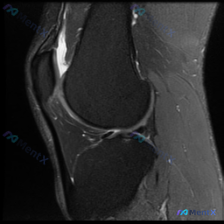

看到说这张膝关节MRI有软骨异常?我整理了完整分析思路

看到大家在讨论这张膝关节MRI,有人提到观察到软骨异常,我整理了完整的影像资料和分析思路,分享出来一起交流。

这是一张膝关节MRI T1加权轴位图像,我们先梳理清楚影像上能看到的客观信息:

- 骨骼结构:清晰显示前方三角形的髌骨和后方的股骨远端,骨髓信号均匀,和皮下脂肪信号相似,未见异常低信号或高信号,排除明显骨髓水肿、肿瘤浸润

- 髌股关节软骨:关节软骨层次连续,未见明确的软骨缺损,也没有软骨下骨质破坏

- 软组织与肌腱:股四头肌腱、支持带纤维结构清晰,腘窝区域肌肉肌腱信号均匀、边界清楚,关节周围软组织没有明显肿胀增厚

- 整体印象:髌骨股骨形态规则,关节间隙正常,没有看到急性创伤骨折、占位性病变或严重退变表现,也没有病理性积液、出血的异常信号

- 现有这张单层面T1图像上,没有发现明确的结构性软骨缺损,也没有软骨下骨的异常改变

综合来看,基于目前给出的这一张影像,最符合证据的判断是:此层面未见明确病理性软骨异常,最可能为正常或生理性改变。如果临床确实高度怀疑软骨病变,必须完善完整多序列多平面MRI才能进一步明确。